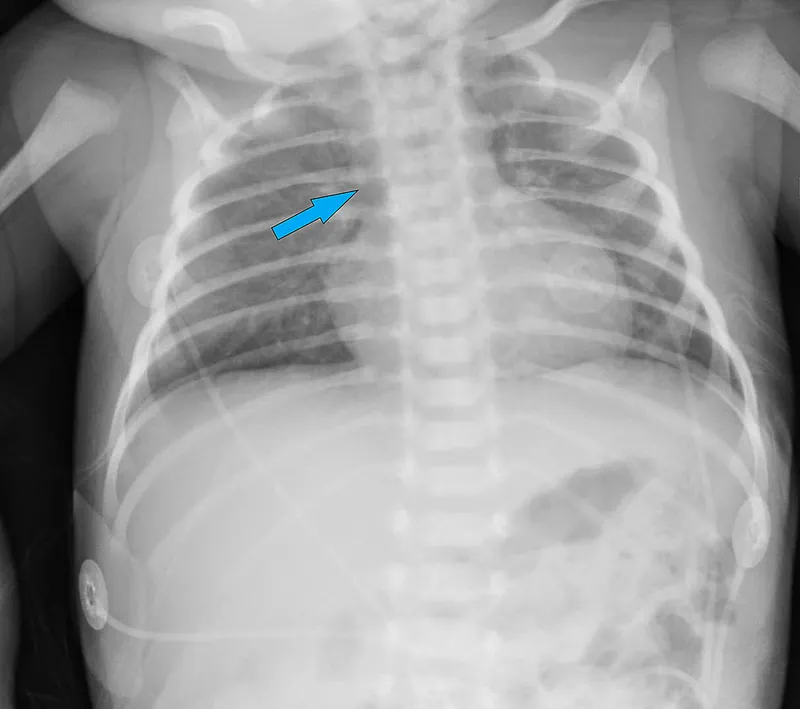

⭐ SCID: Infancy onset, persistent infections, FTT. Absent thymic shadow on CXR is key.